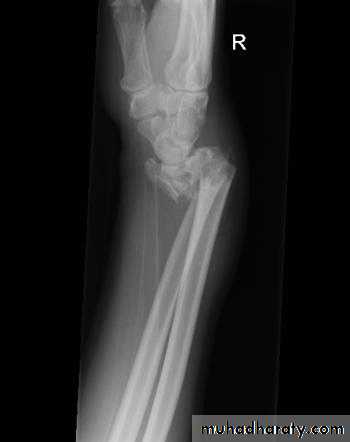

Upper limb

Fall on out stretched hand

40 years male fall on out streched hand

Radial nerve palsy after reduction